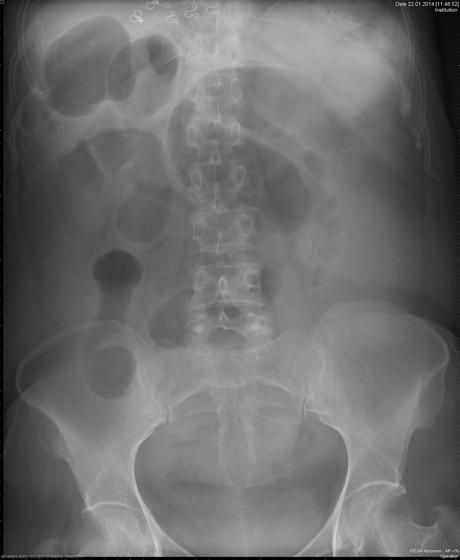

Paciente femenino de 59 años de edad, casada. Ama de casa. Toxicomanias negadas. Alergias negadas. Histerectomia hace 20 años por miomatosis uterina. Antecedente madre finada por cáncer de colon. Refiere que desde finales De mayo del 2017 a perdido más de 7 kilos en 3 meses, pesando 71.100 kilos y ahora 63.900kg (10%), además de dolor epigastrico, punzante, ademas de poca intolerancia a la via oral, vomito en numero de 2 de contenido alimenticio, no biliar. A la exploración signos vitales TA 100/70 mm Hg FC: 80x FR: 20x SatO2: 98% T:36.1 paciente conciente, orientada, palidez (++), normocefalo, buena implantacion del cabello, pupilas isocoricas, mucosa moderadamente hidratadas, cuello sin adenomegalias, cardiorrespiratorio ruidos cardiacos normales, murmullo vesicular normal, abdomen blando depresible, doloroso en epigastrio e hipocondrio izquierdo, no se palpan viceromegalias, giordano izquierdo (+). No se palpan ganglios inguinales. Exploracion rectal no se obsvervan hemorroides o fistulas rectales. Extremidades integras, no edema. Se toma Placa simple de abdomen de pie.

El volvulo sigmoide es una causa de obstrucción del intestino grueso y ocurre cuando el colon sigmoide se tuerce en el mesocolon sigmoide.